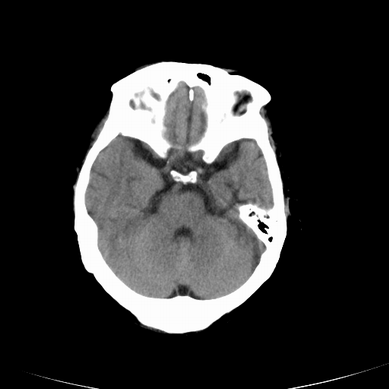

以下是引用jsgdoctor在2008-7-16 23:11:00的发言:[br]左侧大脑中动脉供血区脑梗塞